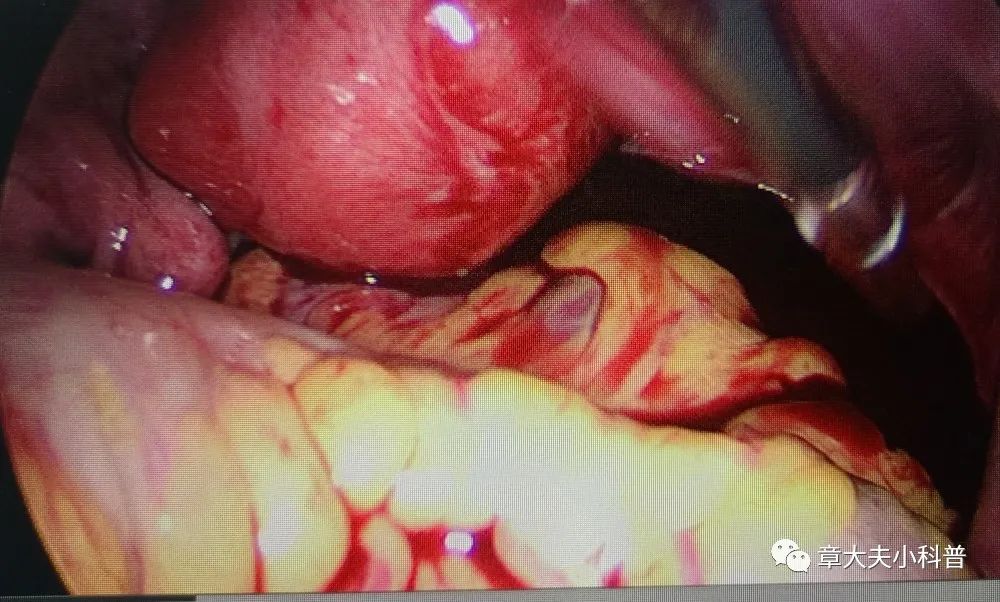

腹腔镜探查

见右侧卵巢

黄体破裂,

腹腔内出血,

1300ml